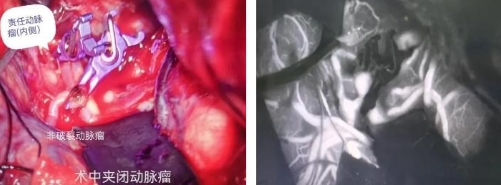

孙国庆主任医师和张鸿涛副主任医师共同完成手术,在高倍显微镜下仔细分离侧裂,在众多血管丛中顺利找到责任动脉瘤。然而,挑战远不止于此。在精心细致的手术过程中,凭借丰富的经验和敏锐的洞察力,孙国庆主任医师在显微镜下发现了另一个隐藏在脑血管结构中的未破裂动脉瘤。这个“潜伏的炸弹”一旦后期破裂,后果不堪设想。

面对这一突发情况,团队临危不乱,经过审慎评估与果断决策,凭借高超的显微手术技术,在一次手术中成功将右侧大脑中动脉的破裂动脉瘤与新发现的未破裂动脉瘤一并完美夹闭,实现了“一举除两患”的最佳效果,避免了患者遭受二次手术的痛苦与风险。

术中荧光造显示动脉通畅,动脉瘤不显影夹闭完全